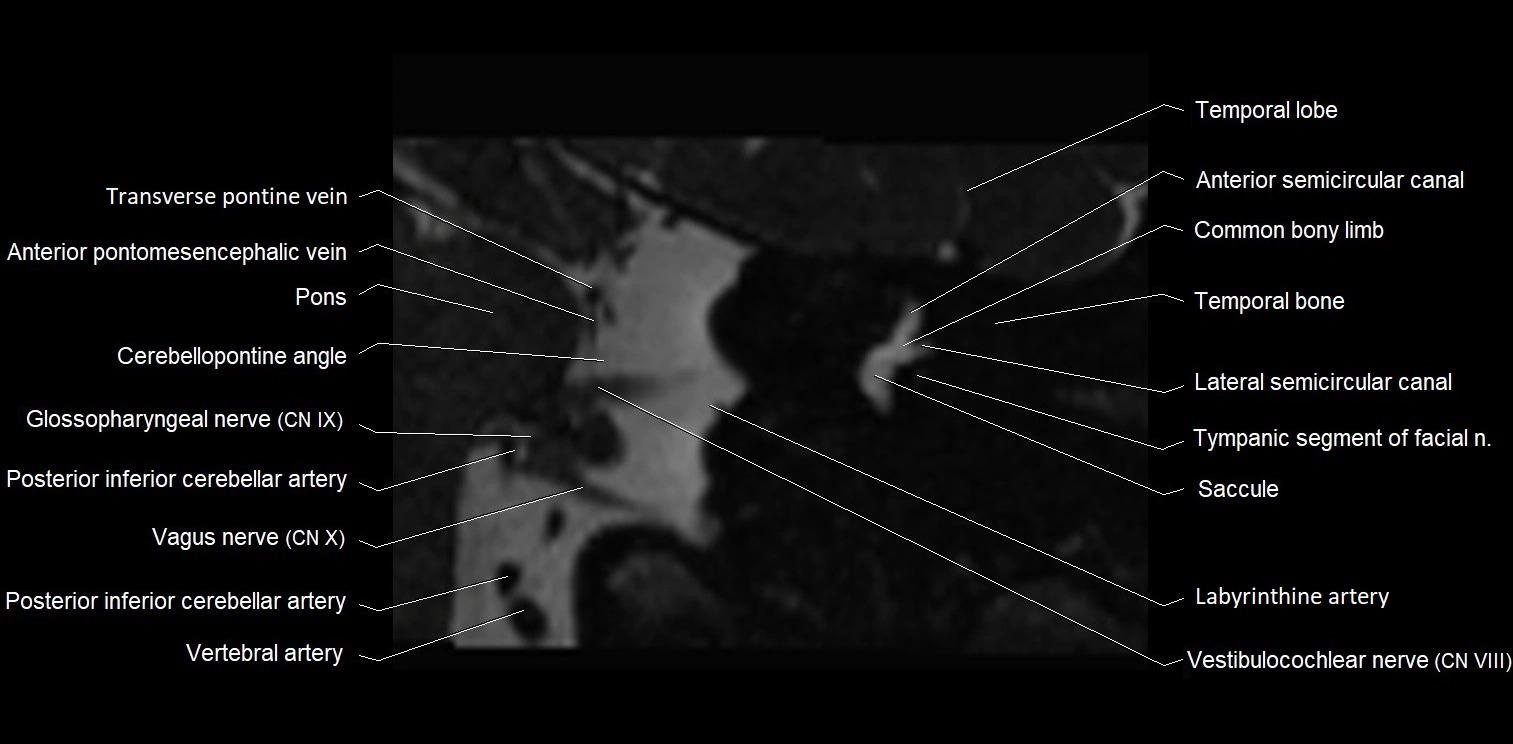

MRI images

image